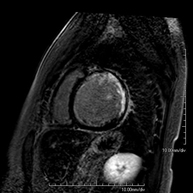

Stress cardiac MRI

This non-invasive diagnostic test yields morphological and functional information about the heart and adjacent structures. These tests can be used to diagnose various congenital and acquired conditions. During the test, the technician will ask the patient to hold their breath several times for 10-15 seconds to obtain the clearest images possible. In the vast majority of cases, intravenous contrast (gadolinium) is required to complete the study. This type of contrast rarely causes adverse reactions. In addition, a drug (adenosine) is administered intravenously to exert an effect on the heart similar to that produced during physical exercise. The images obtained at rest and after pharmacological ‘stress’ are compared to detect deficits in blood supply to the left ventricle of the heart. The test lasts approximately 45–60 minutes. The patient must not consume any foods containing caffeine (coffee, tea, chocolate, cola drinks, etc.) 24 hours before the test. It is not recommended for patients with pacemakers. Patients should nevertheless inform the doctor if they have metal implants and/or surgical clips.